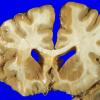

Neuronal Ceroid Lipofuscinosis (NCL) (8)